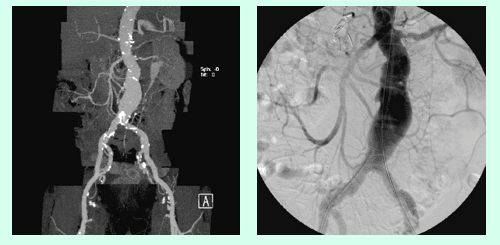

Die Abdomensonographie ist als Screeninguntersuchung und für eine routinemäßige Verlaufskontrolle bei Aneurysmen gut geeignet. Zur exakten Bestimmung der Größe und Morphologie wird jedoch eine Computertomographie (Abb. 1), in Ausnahmefällen eine Magnetresonanztomographie, durchgeführt.

Alternativ zur offenen chirurgischen Therapie eines Aortenaneurysmas besteht die Möglichkeit einer endovaskulären Aneurysmaausschaltung mittels eines Stentgrafts (gewebeummanteltes Metallgittergeflecht). Voraussetzung für die endovaskuläre Therapie ist jedoch eine anatomische Eignung, welche eine ausreichende Weite der Beckengefäße und nötige Verankerungszonen für den Stentgraft mit sich bringt. Die Stentgraft Implantation wird von Interventionellen Radiologen in Zusammenarbeit mit Anästhesist:innen und Gefäßchirurg:innen durchgeführt. Der Eingriff erfolgt unter Spinalanästhesie oder einer Allgemeinnarkose. Der Zugang zum Aneurysma wird üblicherweise durch einen kurzen Schnitt in der Leiste geschaffen. Zur Darstellung des Aneurysmas wird zuerst eine Angiographie der Bauchaorta durchgeführt (Abb.2). Folglich wird unter Röntgendurchleuchtung der Stentgraft über einen Führungsdraht in die Bauchaorta eingebracht und unterhalb der Nierenarterien verankert. Eine Kontrollangiographie nach Stentgraft-Implantation wird zum Nachweis eines guten Ausschlusses des Aneurysmas durchgeführt (Abb.3).

Bei elektiver chirurgischer Sanierung von Descendensaneurysmen wird die 30-Tages-Mortalität mit 5–13% angegeben. Weitere postoperative Komplikationen sind respiratorische Probleme, bis zu 33% neurologische Defizite und renale Insuffizienz bis zu 8%. Die endovaskuläre Stentgraft-Therapie hat deutlich geringere Mortalitäts- und Komplikationsraten und hat als Alternativmethode eine große Bedeutung in der Behandlung von Aneurysmen in der Aorta descendens und des Aortenbogens erlangt. Bei Beteiligung des Aortenbogens sind vorausgehende chirurgische Umbauten von Aortenbogenästen erforderlich, um eine Stentgraft Verankerung zu ermöglichen. Abbildung 4a zeigt ein Aneurysma mit Beteiligung des  Aortenbogens und Abgang der linken Halsschlagader (Arteria carotis) und der linken armversorgenden Arterie (Arteria subclavia) in Nahebeziehung zum Aneurysma. Eine Stentgraft-Therapie kann in solchen Fällen nach Verlagerung (Transposition) der Arteria carotis und Arteria subclavia durchgeführt werden (Abb. 4). Die CT-Kontrolle bestätigt die korrekte Lage des Stent-grafts und den Ausschluss des Aneurysmas.

Die Abbildung zeigt eine CT Angiographie der abdominellen Aorta bei einem 85-jährigen Patienten. Die CTA zeigt ein Aneurysma der Aorta. Aufgrund des geringen Abstandes vom Beginn des Aneurysmas zu den akzessorischen Nierenarterien ist eine Behandlung des Aneurysmas mittels Stentgraftimplantation nicht möglich.